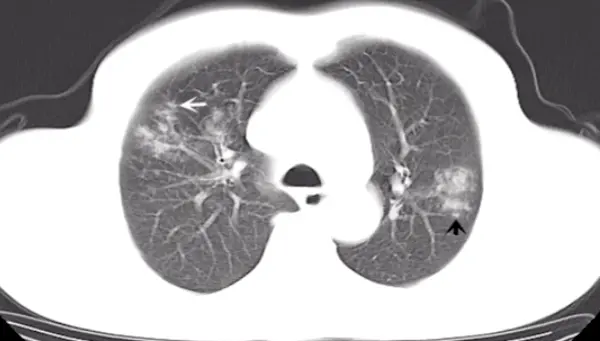

第二题:如下图所示,病变表现为肺实质病变,伴有蜂窝状改变。

第二题答案:肺炎克雷伯菌肺炎,痰液粘稠,有蜂窝状改变。